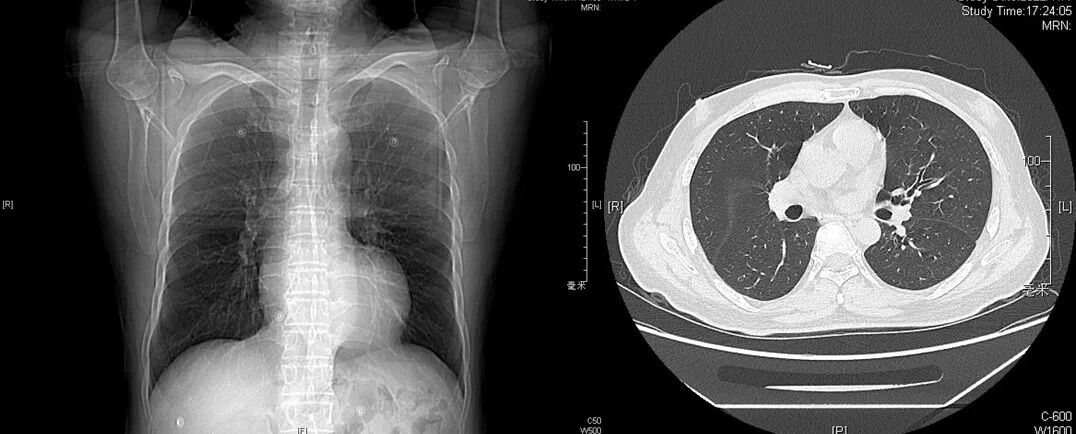

胸部CT

右肺少许索条,右肺尖肺大疱,左心室大、合并室壁瘤,冠脉支架术后,肝多发囊肿。

全主动脉+盆腔动脉增强CT

散在混合性斑块,管腔轻度狭窄;主动脉粥样硬化。